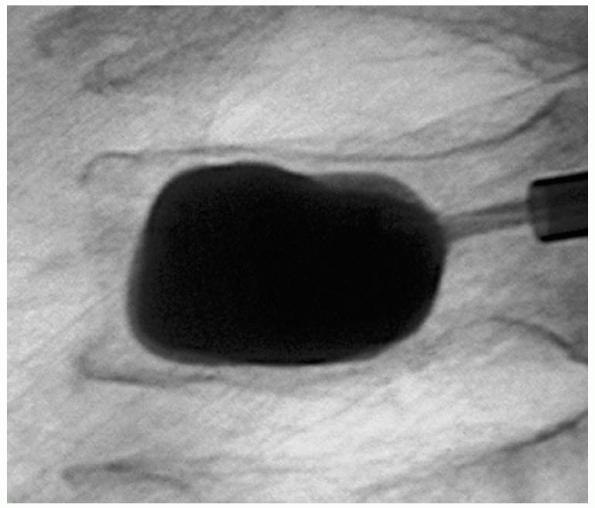

Another method used to improve internal fixation and to avoid bone

resorption is to anchor the pins or screws with polymethylmethacrylate

bone cement. This can be inserted into the bone and allowed to harden

before drilling, or it can be inserted into the screw holes just before

the screws are inserted. The screws can then be tightened after the

cement hardens (Fig. 18-7). If this method is

used, it is important that the cement does not penetrate the fracture

so as to interfere with fracture healing.